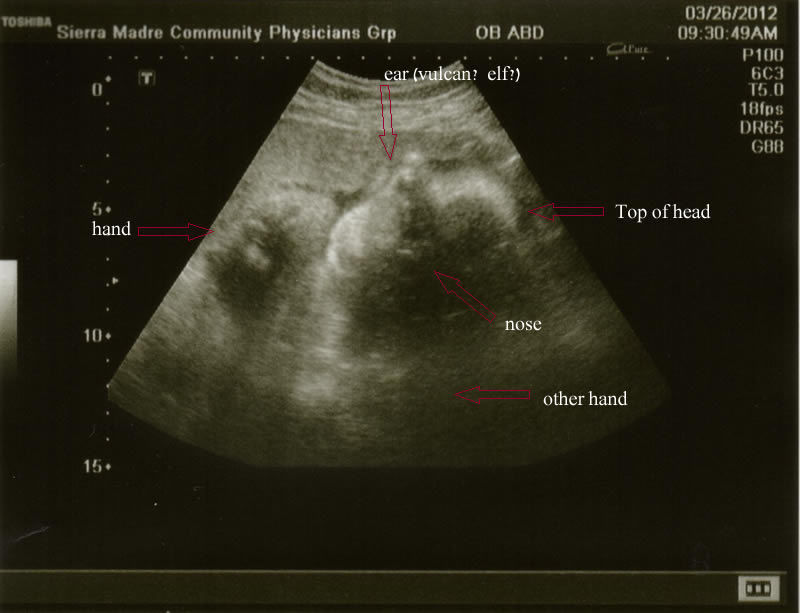

The ultrasound photo (see below) has us laughing hard for multiple reasons...1) it takes several minutes to figure out what the heck this is, 2) once you've got it oriented, you notice what looks like a huge pointy ear coming out of her head, 3) her head itself ends up looking like one of Gary Larson's comic strip kids, and 4) you notice her hands are up & out in front of her like she's either got her face pressed up against a two-way mirror trying to get a peek at us as well, or we've got a prenatal mime-in-a-box on our hands.

Baby O.'s looking great - head down, feet up - in position and all ready to go (but we shall see about that, shan't we?). Her heart is strong; we could see all four chambers on the screen - as well as her arms & legs & fingers & toes.